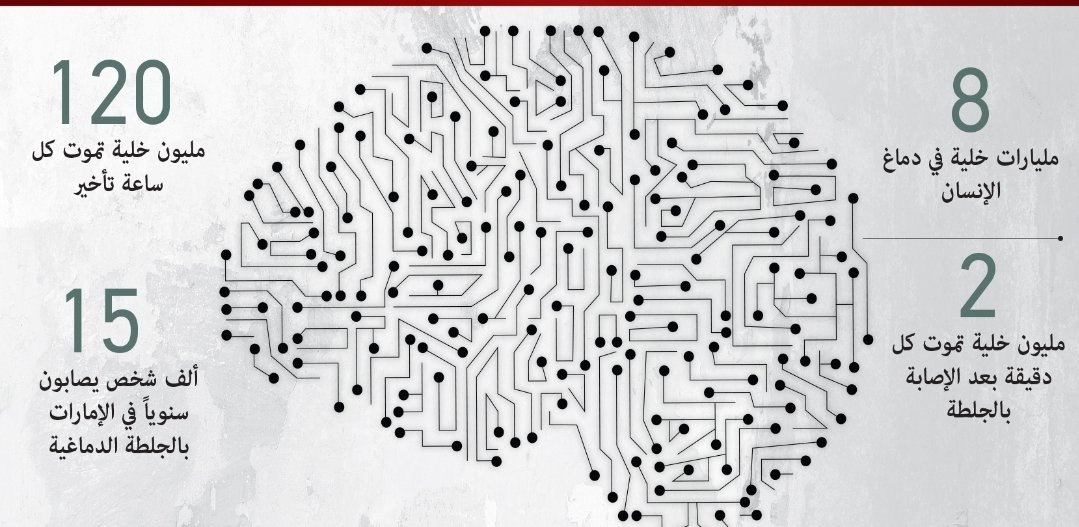

#السكته_الدماغيه_الاقفاريه

💥العلاج

🧠علاج الجلطه الحاليه

♦️مذيب جلطات وريدي

(فقط اول ٤ ساعات ونصف)

♦️قسطرة تداخليه لسحب الجلطه من الشرايين الرئيسيه ان وجدت

(فقط اول ٦ ساعات قد تمتد بشروط)

💥لذلك تذكر

الوقت هو الاهم في علاج السكته الدماغيه

💥لذلك تذكر

الوقت هو الاهم في علاج السكته الدماغيه